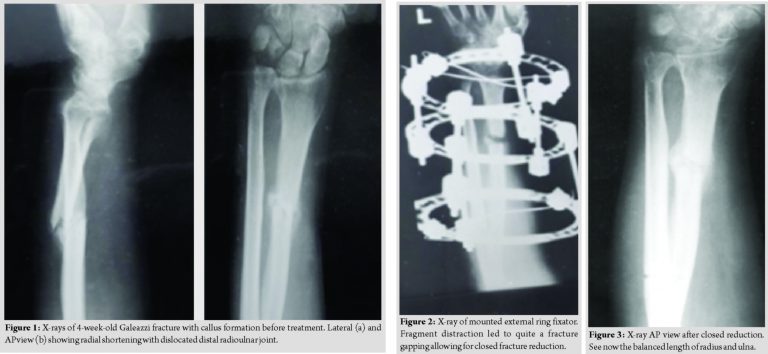

In 1983, a 50-year-old German farmer presented with a 4-week-old Galeazzi fracture. After an injury during work, he had continued his work for a month. Then, he looked for help because the distal fragment of the radial diaphyseal fracture almost perforated the skin. As the radial fracture was dislocated ad longitudinal(shortened), the DRUJ was dislocated. The patient rejected the hospital stay. Therefore, after long discussions with the patient, ambulatory treatment was planned. Local anesthesia was injected into skin and periosteum. Under traction of the forearm with the fingers of the injured extremity being fixed above the elbow and the forearm hanging in a vertical position, the ring fixator was mounted. The radial shaft fracture still was dislocated.

The patient was instructed to daily distract 1 mm in four small steps á 0.25 mm. After 10 days, there was a distraction of 10 mm, and the patient noticed a giving way at the fracture site of the radial diaphysis. As planned, the patient came back to the outpatient clinic, and a closed reduction of the distracted radial shaft fragments was done. The DRUJ dislocation reduced spontaneously at this moment.The farmer picked up his work again– also in the pigsty. He came back with a pin-tract infection, which could be managed with oral broad-spectrum antibiotics. The injury healed without further complications. (Fig. 1–3) depict the course of treatment. After bony consolidation and removal of the external fixator, the patient regained full ROM for a few weeks. The fracture healed, and at the last clinical follow-up, function and ROM were normal on both sides without any sign of subluxation.

Case Report: A50-year-old patient presented 4 weeks after a Galeazzi injury without initial treatment and a shortened radius shaft associated with a dislocated distal radioulnar joint. Through a ring fixator, the fragments were distracted, reduced, and stabilized. Besides an uncomplicated pin-tract infection, the injury healed uneventfully with a very good outcome and very high patient satisfaction still 25 years after the injury.